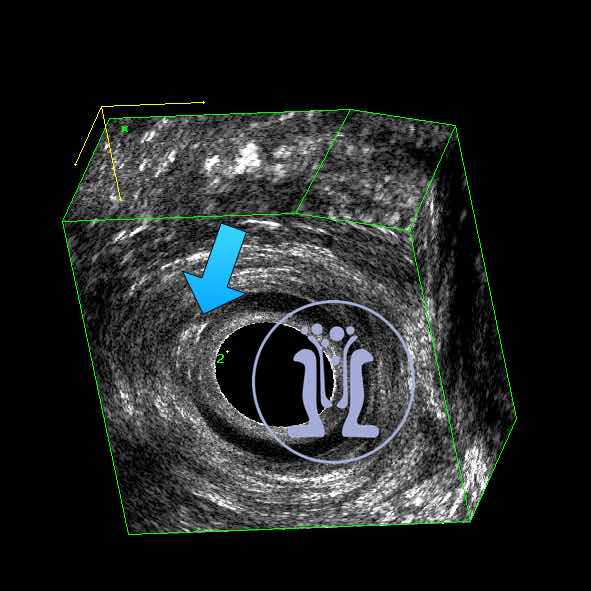

Ασθενής, με ιστορικό σαρκοείδωσης, προσήλθε με ενόχληση στη καθιστή θέση και εκροή διαυγούς υγρού από 10ημερου. Κατά τη κλινική εξέταση, ανευρέθηκε έξω στόμιο συριγγίου, στην 6η ώρα. Το ενδοπρωκτικό υπερηχογράφημα δείχνει χαμηλό συρίγγιο, το οποίο παίρνει ελάχιστο τμήμα εξω σφικτήρα (0.23mm). Προτείνεται διάνοιξη του συριγγώδους πόρου υπό τοπική αναισθησία, η οποία και πραγματοποιείται επιτυχώς χωρίς περαιτέρω δυσκολίες.